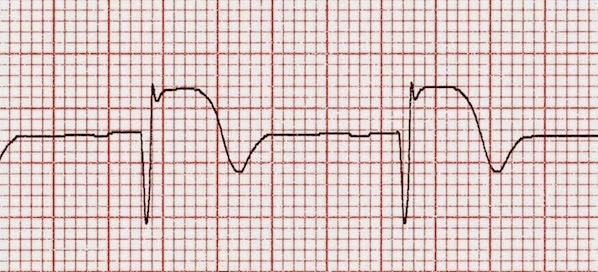

Beta bloqueadores y función cardíaca luego del infarto de miocardio

01 junio 2017

Un estudio británico de cohortes encontró que el uso de beta-bloqueadores luego de un infarto agudo de miocardio no fue beneficioso en ausencia de insuficiencia cardíaca o de disfunción sistólica del ventrículo izquierdo. JACC, 29 de mayo de 2017